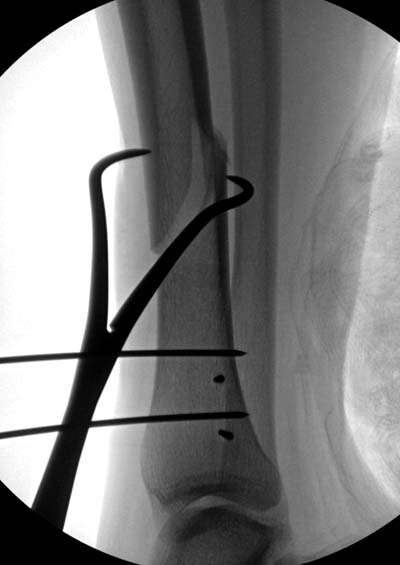

Разбор любого случая кому-то поможет лучше ориентироваться в решении вопросов, потому что в нашей работе встречаются разные связанные и несвязанные с мастерством хирурга ситуации. Возможно, отсутствие полного набора гвоздей повлияло на выбор короткого имплантата, имеется угловая и ротационная деформации. Независимо от локализации, стабильность создается, когда гвоздь проксимально не глубже 1.5 см (облегчает удаление) и дистально доходит до epiphyseal scar.

Кроме этого, имеет значение предварительная репозиция и риминг в центре канала. Интактная малоберцовая иногда затрудняет репозицию, но существуют разные приемы, нп. при застарелом можно применить дистракторы: стержневой или кольца Илизарова, а при свежих - перкутанно Weber clamp.

Мнение о том, что гвоздь сделает репозицию не всегда соответствует истине. Снимки показывают на неудачную попытку исправить направление гвоздя с помощью “поллеров”. Прием возможен только тогда, когда проход риминга в центре канала, иначе толкать гвоздь некуда.

Здесь несколько снимков изолированного перелома большеберцовой с интактной малоберцовой. Weber clamp, блокирующие спицы и риминг в центре канала отрепонировал перелом....